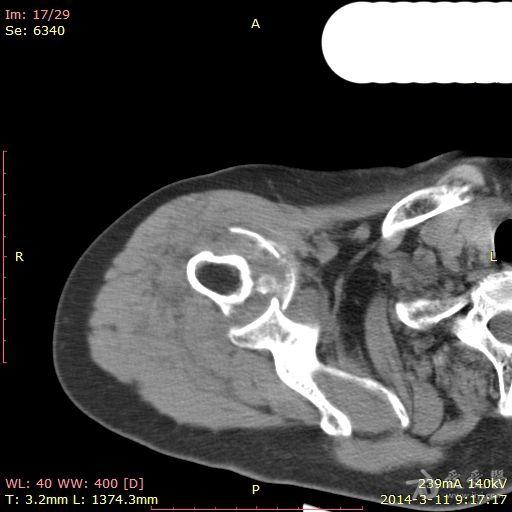

肩关节ct平扫图片,正常人肩膀ct图片

肩关节外伤平扫

肩关节ct

肩关节ct扫描图片